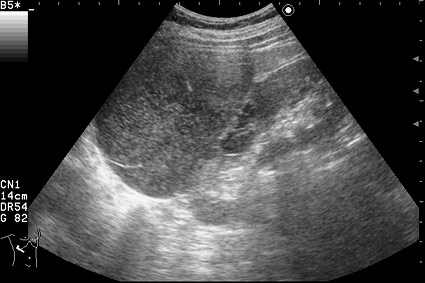

Изменения правой почки у женщины 55 лет

Периодически беспокоят несильные боли справа, чувство дискомфорта.

Сонограмма правой почки.

Нет, это кистоподобное образование, связанное с почкой.

Необычнвя картинка. В голову приходят самые "сумашедшие" предположения (в т.ч. малигнизация кисты, но нет кровотока, нагноившаяся киста, но нет реакции ее стенки; киста с густым содержимым, но отчего оно так загустело?). Просветите нас, пожалуйста.

Почечно-клеточный рак правой почки, кистозная форма.

Но только по густому содержимому кистозного компонента. Стенка тонкая, кровоток не прокрашивается (единичный мелкий срез сосуда в центре образования больше похож на артефакт, а м.б. им и является).

Если бы в этом случае и содержимое было бы более "жидким", вероятность постановки правильного диагноза была бы минимальной.

Я в своем заключении предположил кисту с внутренним кровоизлиянием.

И ошибся.